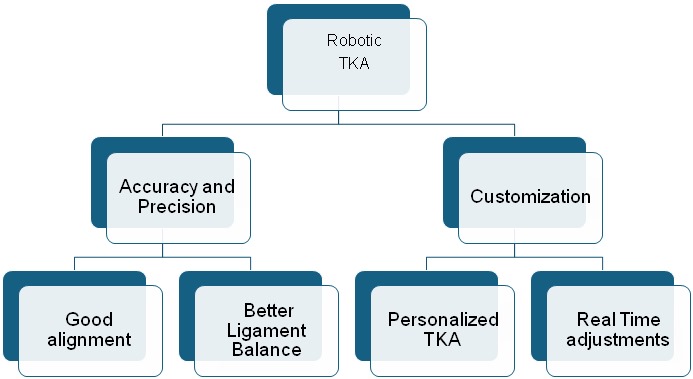

The last decade has seen a dramatic shift in the usage of robotic in total knee replacement(TKR). In India the scenario has dramatically altered in the last couple of years with the widespread usage of robotics to improve outcomes in TKR. The advantages of TKA have been shown in the flow chart below.

Robotic knee helps us to customize the alignment to the patient and not the patient to the alignment. The advantages of robotic knee is again Customization to patient needs, accuracy of the bone cuts, better ligament balancing and intraoperative immediate feedback for correction and modulation of the process for better outcomes.